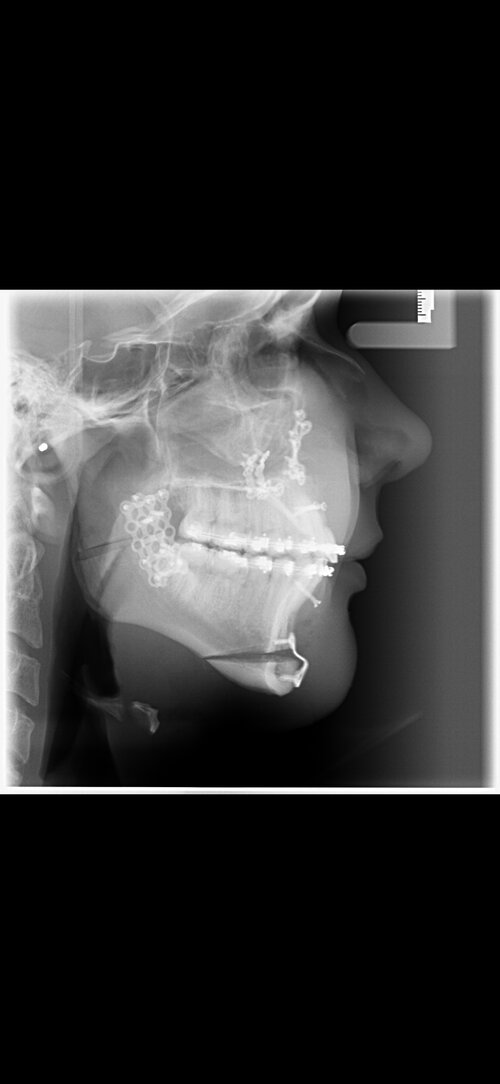

These are my CTs, how big do yall think i will ascend?

Before and after:

• Fabian_Noah_Luca_14012026_152010.png

Fabian_Noah_Luca_14012026_152010.png

2.5 MB · Views: 0